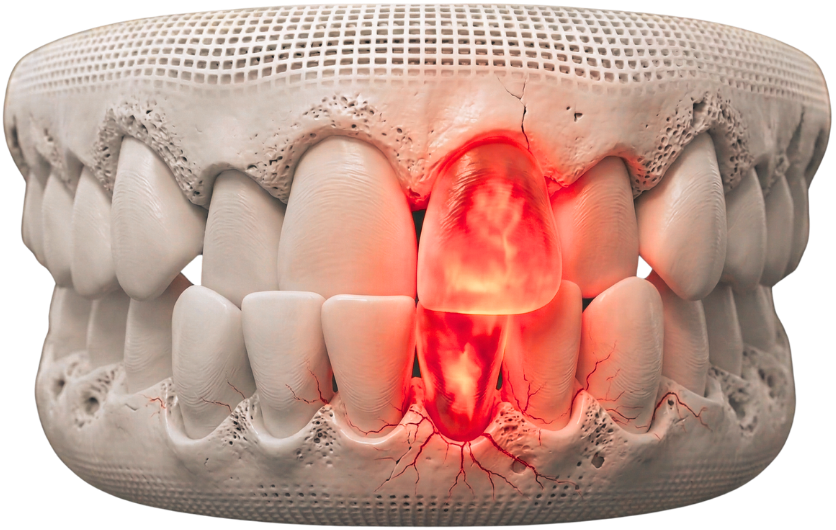

Microscopic Root Canal

Need for a Microscopic Root Canal?

Severe Tooth Pain

Persistent or sharp pain may indicate deep infection within the tooth that requires immediate attention.

Swelling or Abscess

Infection can lead to swelling, pus formation, or gum tenderness around the affected tooth.

Detailed Diagnosis & Imaging

We use advanced diagnostics and magnification to accurately identify the extent of infection and plan treatment.

Precision Cleaning & Shaping

Infected pulp is carefully removed, and the canals are cleaned and shaped under microscopic guidance.